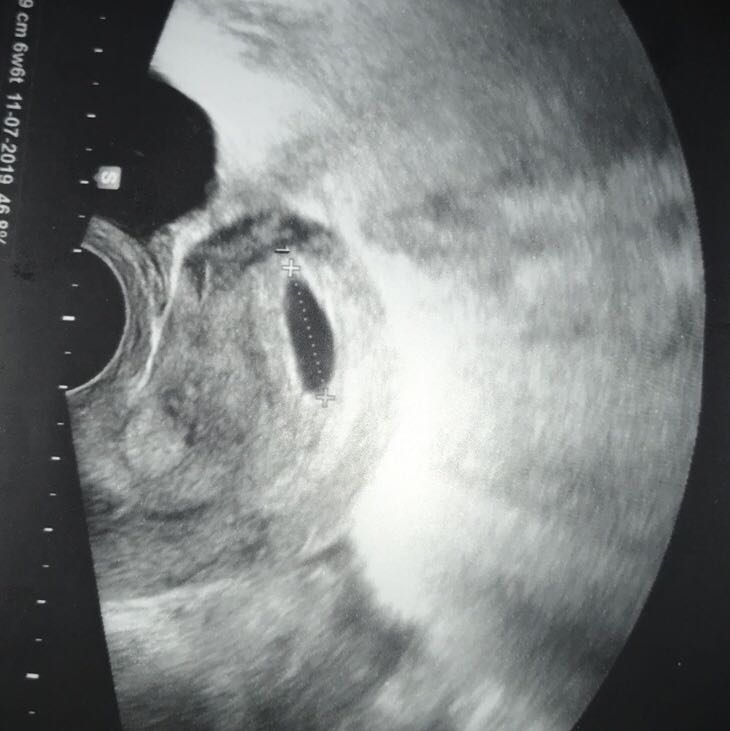

SSW das Gestationsalter um 4 e unterschätzt (3,7 mm Differenz im CRL), dafür in der 11–14 SSW um einen (0,8–1 mm) überschätzt Die aus dem Jahr 19 stammenden HadlockKurven unterschätzen das Gestationsalter in der 6 SSW um 3 e (2,7 mm) und überschätzen es in der 14 SSW um 2 e (4,8 mm). Das Ultraschallbild der 6SSW zeigt zu Beginn der Schwangerschaftswoche den Dottersack Die Fruchthöhle ist der Bereich, in dem der kleine Embryo heranwächst Den kleinen Embryo wirst du gegen Ende der 6SSW gut erkennen Bedenke, dass die Fruchthöhle bei jeder Schwangeren unterschiedlich groß ist. Ultraschallbild 41 SSW Ultraschall in der 5 4 Schwangerschaftswoche Das tut sich in der 4 SSW SSW 4 So entwickelt sich das Baby (Sebastian Kaulitzki / Fotoliacom) Am Ende der vierten Schwangerschaftswoche ist die Einnistung des Keimlings in die Gebärmutter abgeschlossen Bis aus diesem Zellhäufchen ein Baby wird, ist es noch ein.

6 SSW Das ist jetzt wichtig Traurig, aber ein Thema, das Sie nicht außer Acht lassen sollten Selbst, wenn es mit der Befruchtung der Eizelle geklappt hat, kann es auf dem Weg zur Gebärmutter Probleme geben, die eine Schwangerschaft doch noch verhindern Bei einer Eileiterschwangerschaft beispielsweise nistet sich die befruchtete Eizelle im Eileiter ein. Ultraschallbild 6 SSW Auf dem Ultraschall in der 6 SSW ist dein Baby schon deutlich zu erkennen Allerdings hat es auf dem Bild noch eher die Form einer Bohne und du wirst kaum Details erkennen Dabei ist seit der Befruchtung schon viel passiert Aus einem Zellhaufen hat sich in 28 en (Ende SSW 6) ein Embryo mit erkennbarem Kopf, Arm und. Das Ultraschallbild der 6SSW zeigt zu Beginn der Schwangerschaftswoche den Dottersack Die Fruchthöhle ist der Bereich, in dem der kleine Embryo heranwächst Den kleinen Embryo wirst du gegen Ende der 6SSW gut erkennen Bedenke, dass die Fruchthöhle bei jeder Schwangeren unterschiedlich groß ist.

Die 6SSW ist die zweite Woche im zweiten SchwangerschaftsmonatSie hält eine schnelle Entwicklung für das Baby im Bauch der Schwangeren bereit und bei der Mutter verstärken sich die Beschwerden und Anzeichen typischer SchwangerschaftssymptomeNachdem in der 5SSW das Herz mit dem ersten Herzschlag seine Arbeit aufgenommen hat, setzt nun das Wachstum weiterer Körperteile ein. Ultraschallbild 53 SSW Ein Ultraschallbild aus dem 3 der 6 Schwangerschaftswoche (53) Dieser Befund ist eher typisch für die Mitte der sechsten SSW Meist stellt sich die Fruchthöhle nun nicht mehr ganz rund wie in der 5 SSW dar, sondern erscheint leicht queroval. Der Embryo in der 6 SSW In der 6 SSW ist der Embryo etwa vier Millimeter groß Die Befruchtung war erst vor etwa drei bis vier Wochen, doch im Ultraschall sieht man bereits ein kleines gekrümmtes Würmchen mit schnell schlagendem Herz Etwa 150 Mal in der Minute schlägt es – doppelt so schnell wie Ihr eigenes.

Ultraschallbild 6 SSW Auf dem Ultraschall in der 6 SSW ist dein Baby schon deutlich zu erkennen Allerdings hat es auf dem Bild noch eher die Form einer Bohne und du wirst kaum Details erkennen Dabei ist seit der Befruchtung schon viel passiert Aus einem Zellhaufen hat sich in 28 en (Ende SSW 6) ein Embryo mit erkennbarem Kopf, Arm und. SSW auf einem Ultraschallbild zu sehen In der 3 SSW lässt sich leider noch nichts auf dem Ultraschallbild erkennen Du musst Dich noch etwas gedulden Erst ab der 6 SSW kann der etwa 4 mm große Embryo sicher auf dem Ultraschall erkannt werden Ab der 8 SSW ist der Embryo auch zum ersten Mal für die Eltern klar ersichtlich. Der Embryo in der 6 SSW In der 6 SSW ist der Embryo etwa vier Millimeter groß Die Befruchtung war erst vor etwa drei bis vier Wochen, doch im Ultraschall sieht man bereits ein kleines gekrümmtes Würmchen mit schnell schlagendem Herz Etwa 150 Mal in der Minute schlägt es – doppelt so schnell wie Ihr eigenes.

Das Ultraschallbild der 6SSW zeigt zu Beginn der Schwangerschaftswoche den Dottersack Die Fruchthöhle ist der Bereich, in dem der kleine Embryo heranwächst Den kleinen Embryo wirst du gegen Ende der 6SSW gut erkennen Bedenke, dass die Fruchthöhle bei jeder Schwangeren unterschiedlich groß ist. Ultraschallbild bei 60 SSW Ab der 7 Schwangerschaftswoche beginnt dein Baby rasant zu wachsen Jeden wird es ungefähr einen Millimeter größer Bei der Ultraschalluntersuchung kann der Frauenarzt ab sofort die Größe des Embryos ausmessen. Alle stolzen Mütter möchten ihre "Pünktchen" oder "Bohnen" der gesamten Welt zeigen Falls du von deinen eigenen Ultraschallbildern nicht genug bekommen kannst, haben wir hier weitere tolle Bilder für dich gesammelt alle aus dem ersten Trimester!.